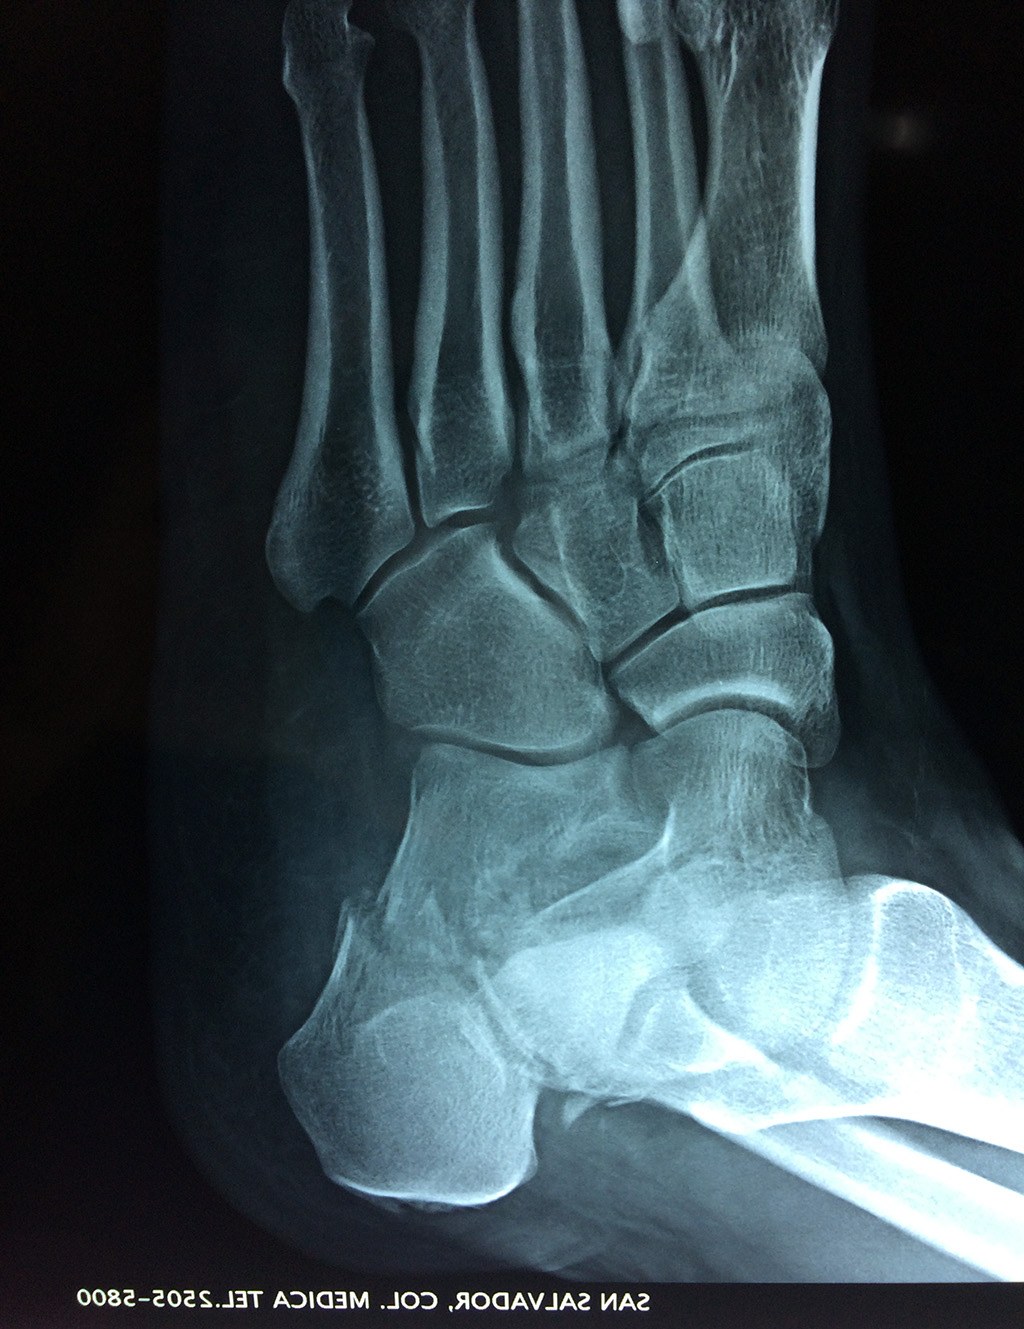

El calcáneo (del latín Os calcis) es un hueso del pie (tarso), corto, asimétrico, de forma cúbica irregular, con seis caras: superior e inferior, laterales y anterior y posterior, de las cuales dos son más o menos articulares.

Este hueso constituye el talón del pie. Se encuentra en la parte inferior de la primera fila del tarso. Se articula con el astrágalo por arriba y con el cuboides por delante. Constituye el primer punto de apoyo del pie durante la marcha, situándose en una de las zonas peor irrigadas del cuerpo y protegido plantarmente por la almohadilla plantar de tejido adiposo, con función amortiguadora.

En su cara posterior recibe la inserción del tendón más plantar, implicada en diversas enfermedades como la fascitis o el espolón calcáneo. La posición del calcáneo en relación al astrágalo (articulación subastragalina) y al suelo determinan la posición de retropié en varo, en valgo o neutra.

Los retropiés varos y sobre todo, los retropiés valgos, son responsables de distintas enfermedades del aparato locomotor y contribuyen a que aparezcan alteraciones de la marcha normal fisiológica, con consecuencias clínicas importantes (dolor, sobrecargas, aplanamiento, fatiga muscular, juanetes, etc.) tanto a nivel de pie como a nivel del miembro inferior.

De todo esto se deriva que su posicionamiento espacial es muy importante para contribuir a una marcha correcta y a la salud del resto del conjunto articular del pie.